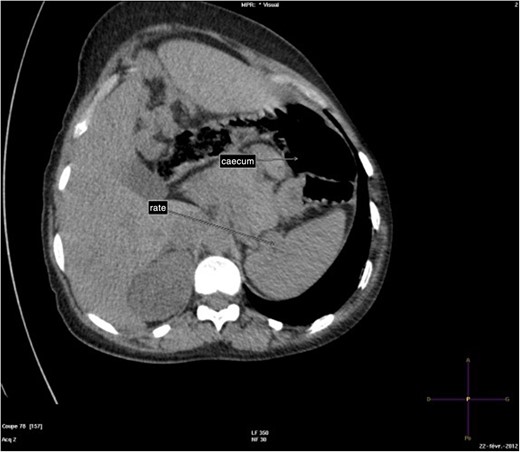

The abdominal-pelvic CT-scan showed a pre-splenic left position of the caecum and right colon, with no part of the colon on the right. The radiologist concluded that the patient was suffering from a complication of intestinal malrotation (IM) (Figs 1, 2, 3).

Abdominal-Pelvic CT-scan, non-contrast enhanced, in the sagittal plan, tenth dorsal vertebra level.